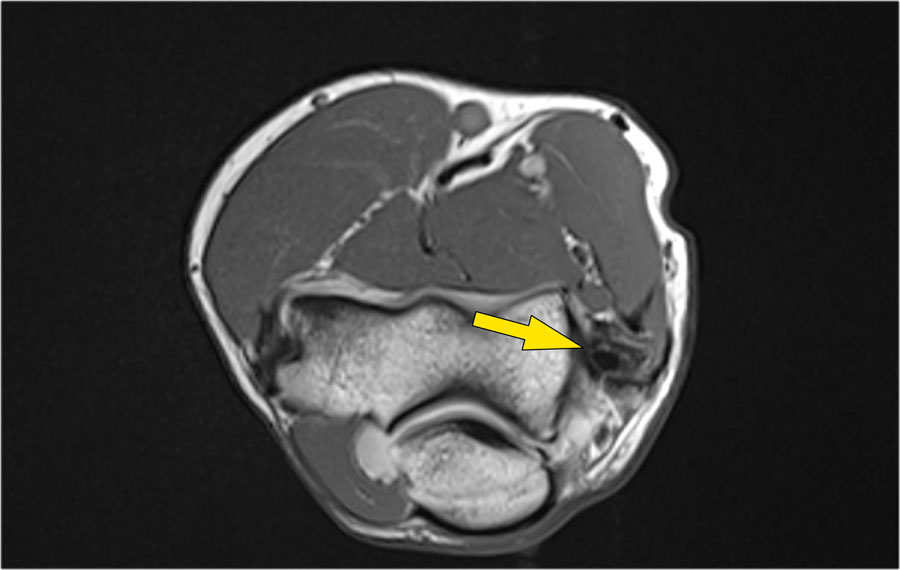

Những hình ảnh này của một nam giới 23 tuổi bị ngã chống tay khi đang trượt ván hai tuần trước.

Khi khám lâm sàng, ghi nhận giảm biên độ vận động khớp khuỷu và đau khi ấn dọc theo mặt ngoài.

Cấu trúc nào nằm phía sau chỏm quay trên hình ảnh cắt ngang?

Cấu trúc phía sau chỏm quay là dây chằng vòng.

Nó không đều và dày lên do hậu quả của trật khớp ra sau.